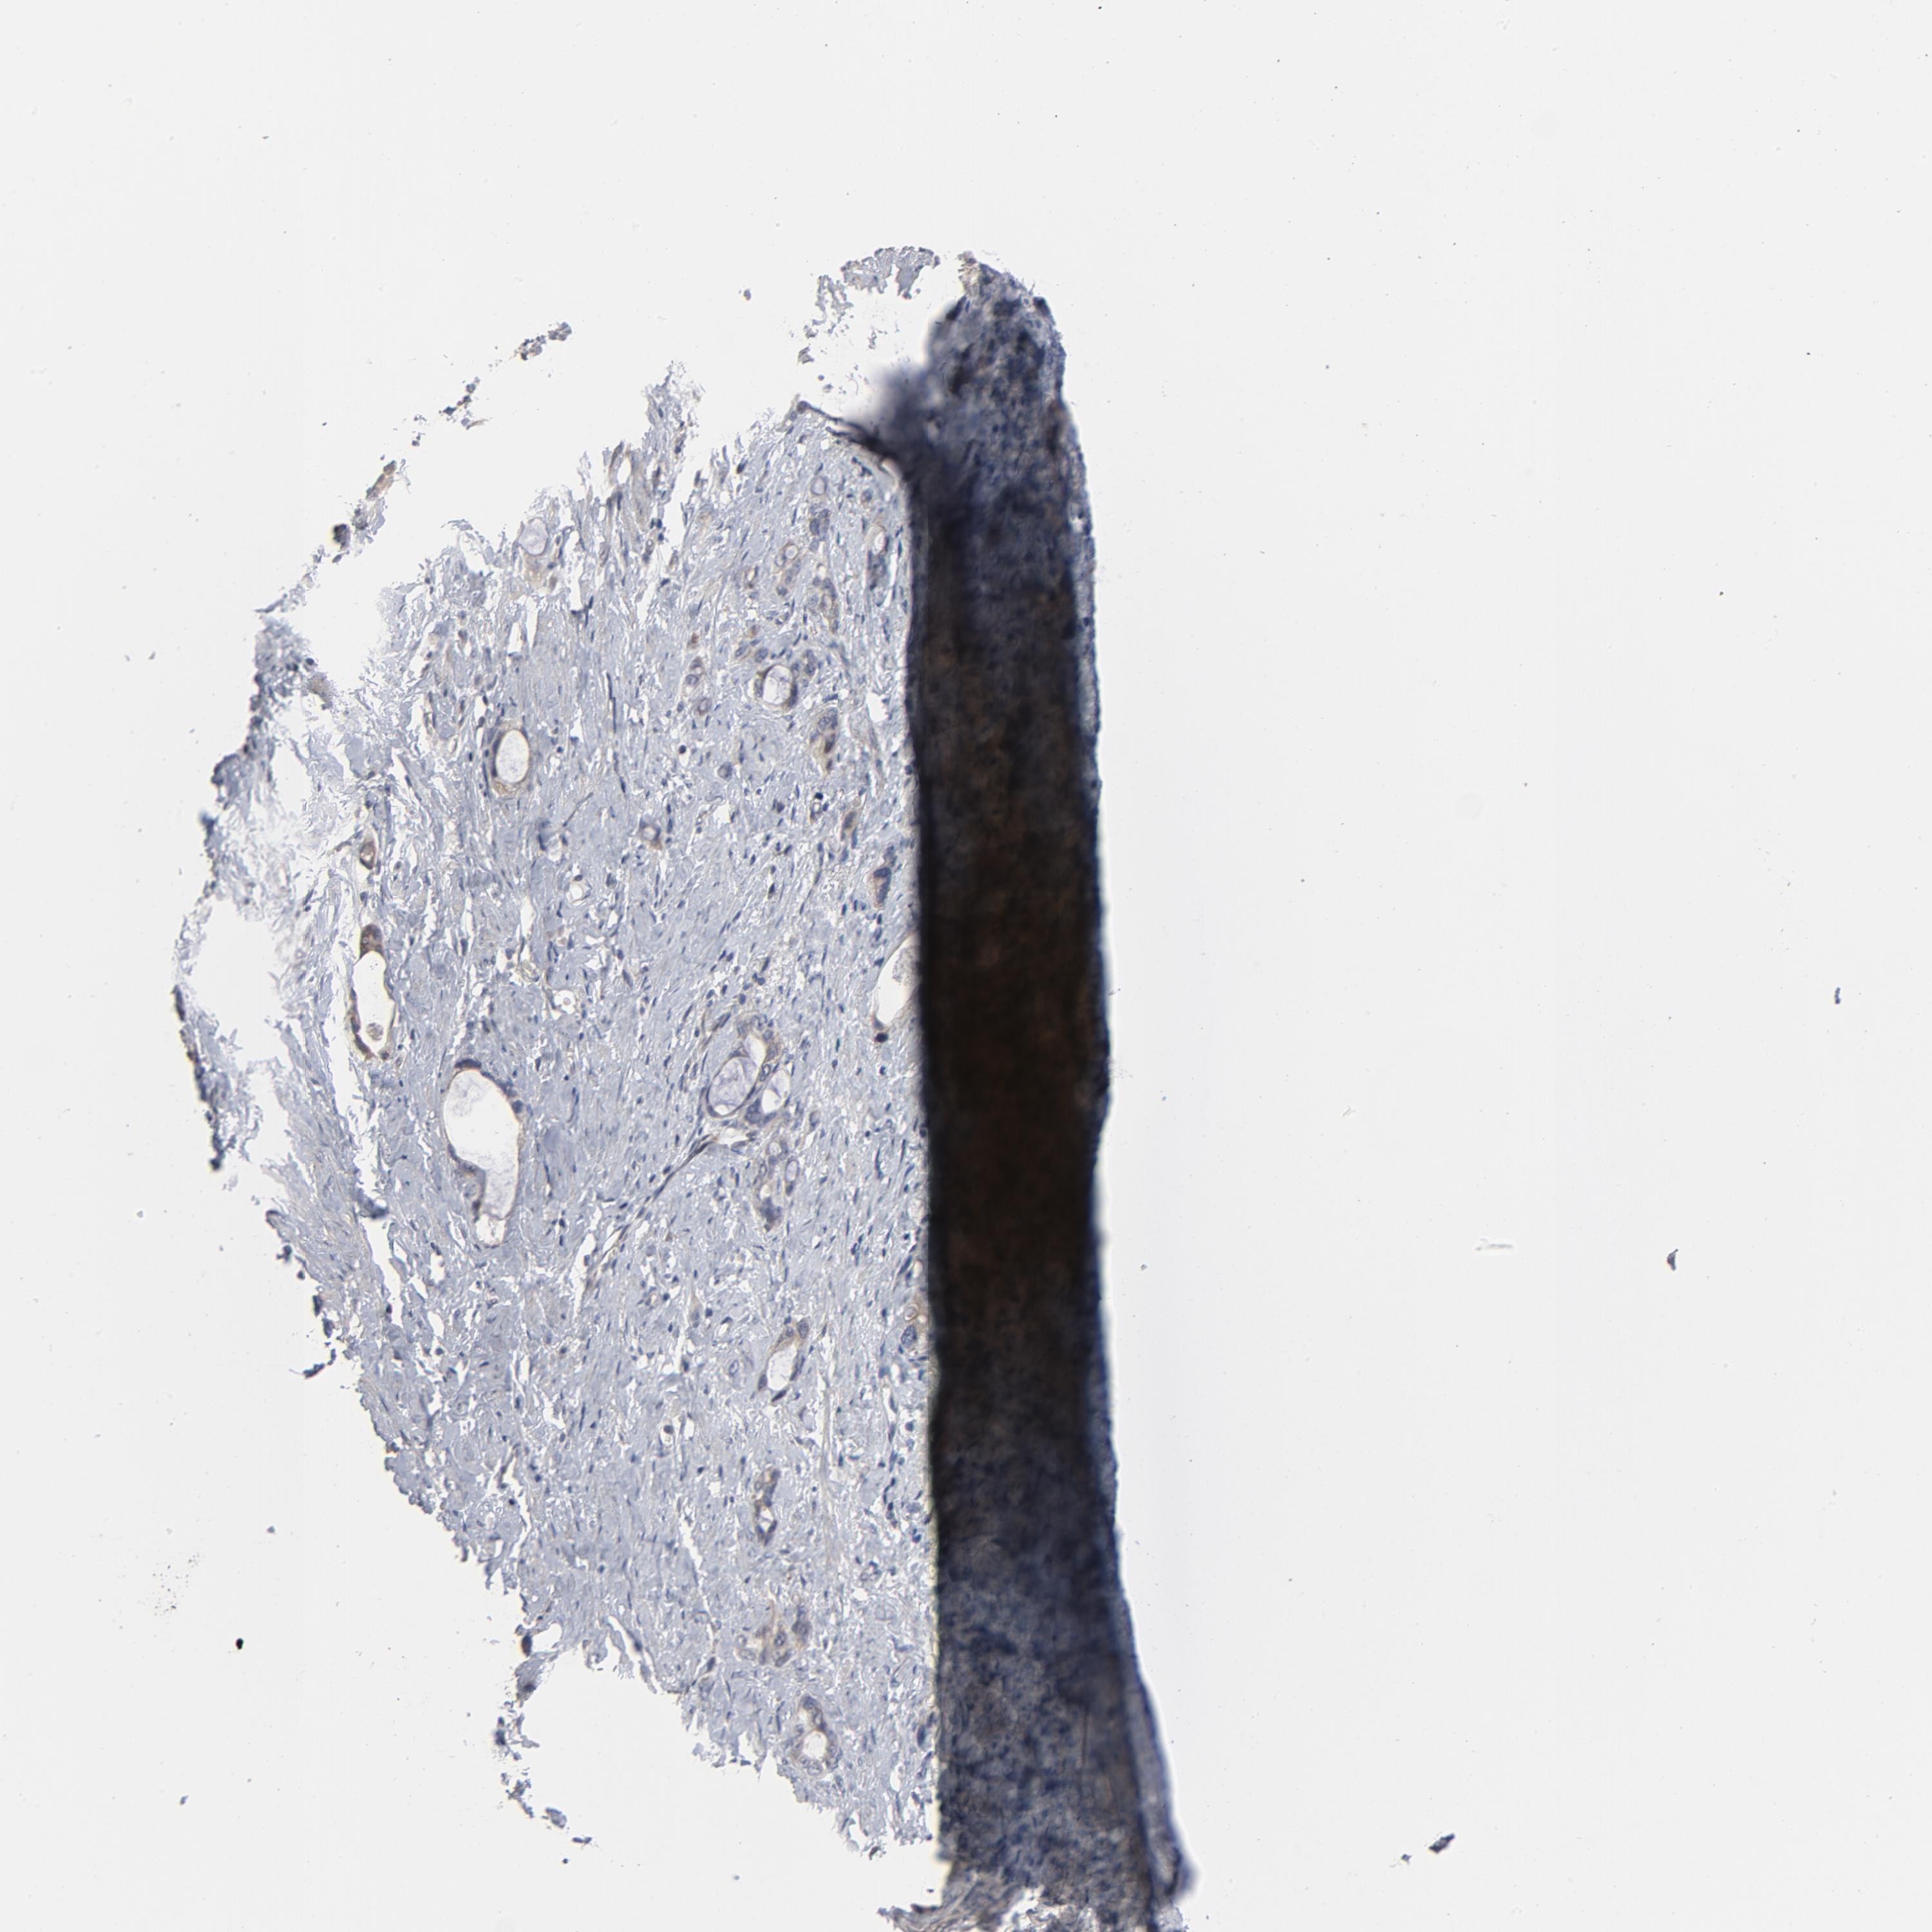

STOMACH CANCER - Protein expressioni

A mouse-over function shows sample information and annotation data. Click on an image to view it in a full screen mode. Samples can be filtered based on level of antibody staining by selecting one or several of the following categories: high, medium, low and not detected. The assay and annotation is described here.

Note that samples used for immunohistochemistry by the Human Protein Atlas do not correspond to samples in the TCGA dataset.

Antibody stainingi

Antibody staining in the annotated cell types in the current human tissue is reported as not detected, low, medium, or high, based on conventional immunohistochemistry profiling in selected tissues. This score is based on the combination of the staining intensity and fraction of stained cells.

Each image is clickable and will lead to virtual microscopy that enables deeper exploration of all samples and also displays staining intensity scores, fraction scores and subcellular localization as well as patient and tissue information for each sample.

Antibody HPA048630

Antibody HPA061142

Antibody CAB004026

Staining

High

Medium

Low

Not detected

Intensity

Strong

Moderate

Weak

Negative

Quantity

>75%

75%-25%

<25%

None

Location

Nuclear

Cytoplasmic/membranous

Cytoplasmic/membranous,nuclear

Adenocarcinoma, NOS

Adenocarcinoma, High grade